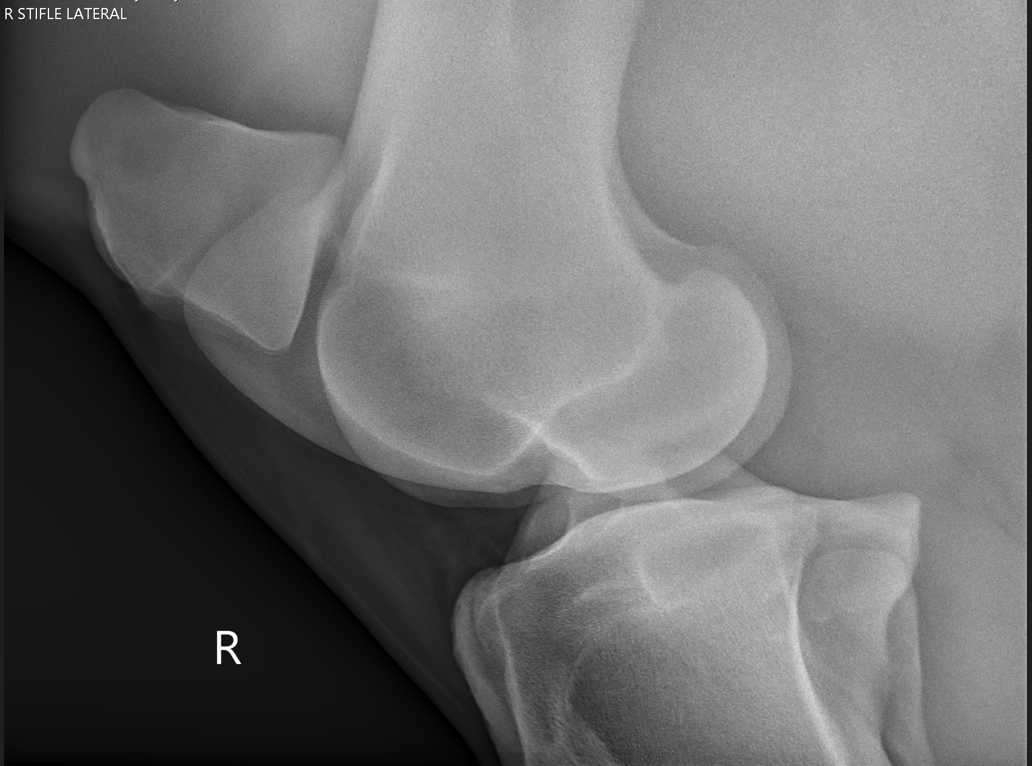

Veterinary radiography (also known as x-rays) provides an in-depth, noninvasive way to image the bones and internal organs of animals. These radiographs help veterinarians diagnose and monitor various conditions, such as bone fractures, dental issues, and internal organ problems.

The process involves positioning the animal and capturing images that can reveal abnormalities

and guide treatment decisions. Veterinary radiography is a critical tool for providing accurate and effective care to animals.